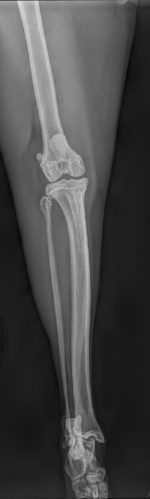

Gato macho castrado de 3 años con cuadro de cojera de la extremidad pélvica izquierda de 2 meses de evolución con respuesta parcial al tratamiento con AINEs. En consulta, el paciente presenta una cojera de extremidad pélvica izquierda grado 3/6 y dolor a la exploración de la rodilla izquierda con efusión articular. El resto del examen físico es compatible con la normalidad. Se realizan radiografías de la rodilla izquierda en proyecciones medio-lateral y caudo-craneal (Figuras 1A y 1B).

En la radiografía se observa un aumento de la opacidad de la grasa infrapatelar, hallazgo compatible con efusión articular. También pueden identificarse pequeñas mineralizaciones en la zona de proyección de los ligamentos cruzados, indicativas de una posible avulsión ligamentaria o de la formación de osteofitos y entesofitos secundarios a la inestabilidad articular crónica. Estos cambios radiográficos, junto con signos de osteoartritis, son característicos de la rotura del ligamento cruzado craneal y reflejan la respuesta degenerativa de la articulación ante la pérdida de estabilidad.

Figura 1A y 1B. Proyección mediolateral y posteroanterior de la rodilla del paciente felino.